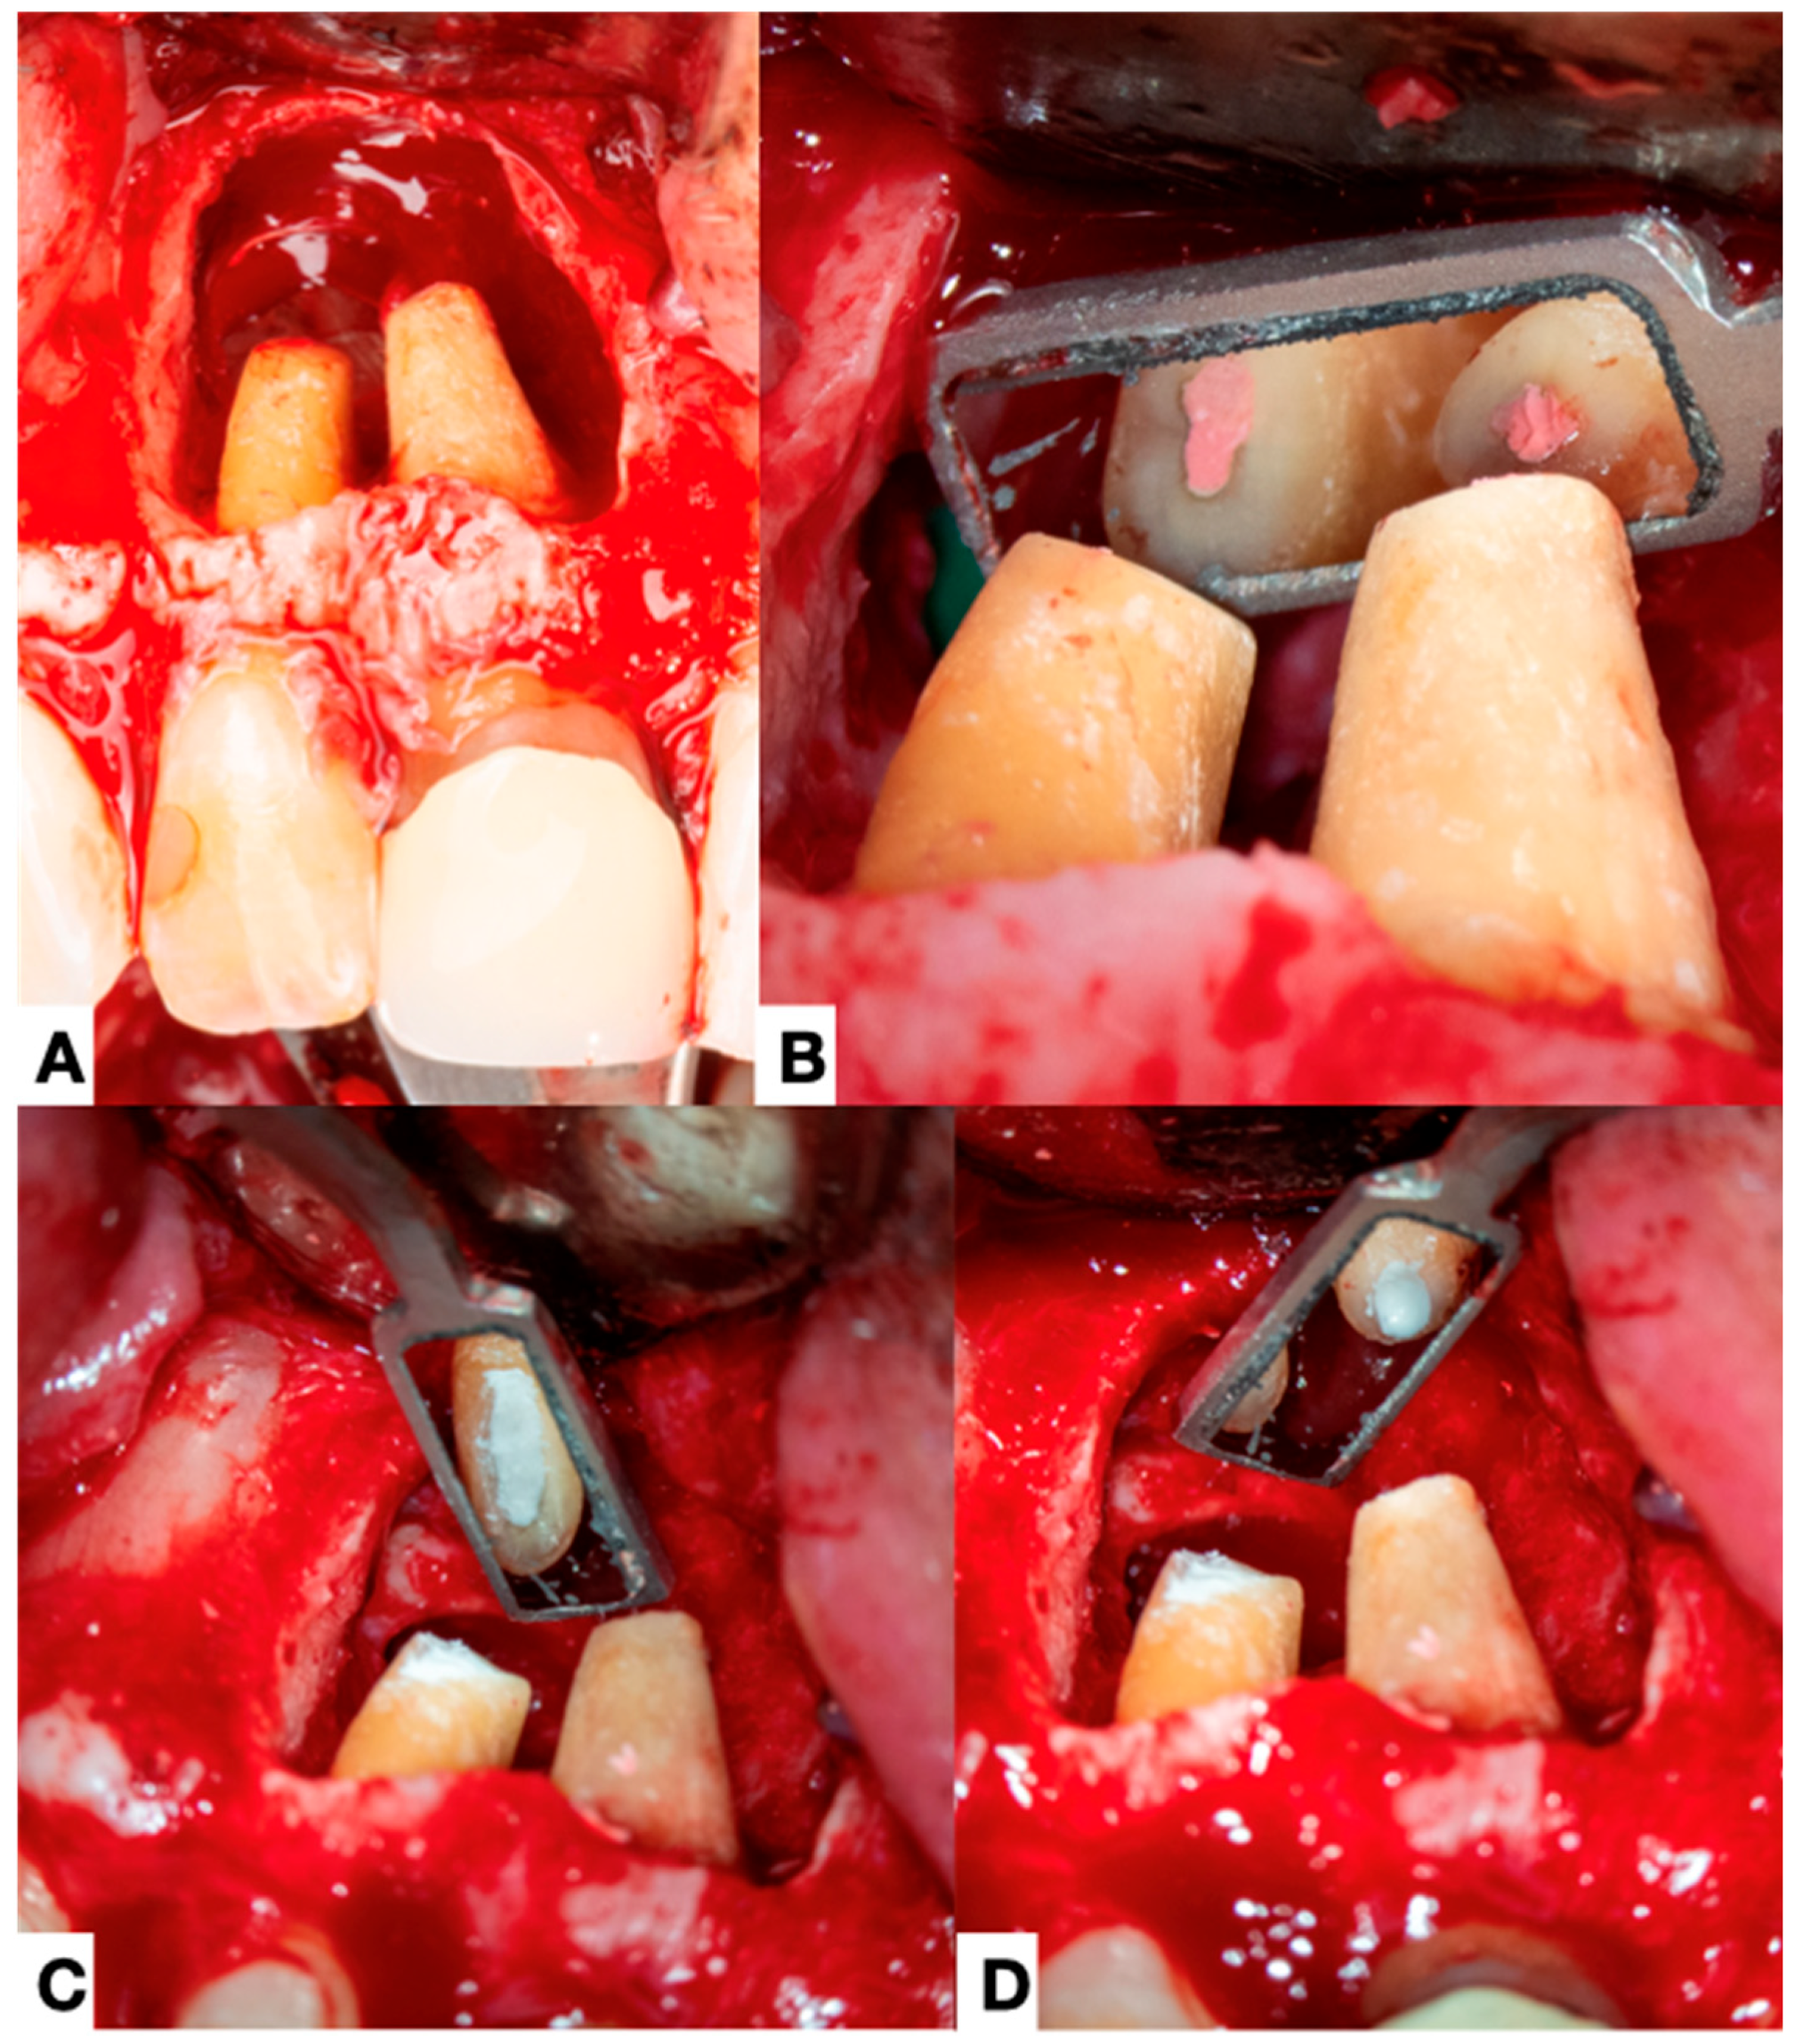

3.1.3. Adjunctive Procedures and Treatment Approaches

3.1.4. Extraradicular Biofilm and Calculus Formation

4.4. Treatment of the Extraradicular Infection

- Ricucci, D.; Candeiro, G.T.; Bugea, C.; Siqueira, J.F., Jr. Complex Apical Intraradicular Infection and Extraradicular Mineralized Biofilms as the Cause of Wet Canals and Treatment Failure: Report of 2 Cases. J. Endod. 2016, 42, 509–515. [Google Scholar] [CrossRef]